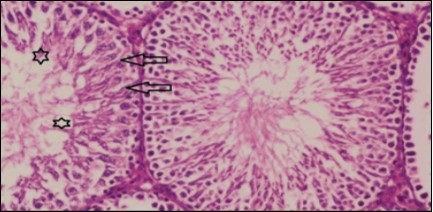

Kidney Histopathological Observations

Kidney sections of diabetic rats showed an increase in mesangial cell and matrix of glomeruli with increase in glycogen deposition and hyalinization of arterioles with thickened basement membranes of proximal and distal convoluted tubules. These changes will lead to progressive reduction in the filtration surface of the glomeruli 35. Histological examination of the kidney of the control rats showed normal structure of renal glomerular. The proximal and distal tubules were lined with normal epithelium (Figure 13). The diabetic rats showed tubular casts, inflammatory cellular infiltration and glomerular atrophy (Figure 14). Kidney of rats in groups (3 and 4) showed some glomeruli return to be normal (G). Focal tubules casts (T) in Fenugreek group and some normal tubules in the Glimepiride group with no inflammatory cellular infiltrate in both groups (Figure 15 and Figure 16). However, kidney of rats in group (5) showed normal glomerular (G), normal tubules (T) with no tubular casts (Figure 17).

Figure 14.Photomicrogragh of kidney section of diabetic rat showing a trophy of Bowman,s capsules and damage of glomeruli (arrow) and damage of distal and proximal tubules with congested blood vessels (star) . (H&E) (100Px).

Figure 16.Photomicrogragh of kidney section of treated rat with Glimepiride showing improvement of Bowman,s capsules and partial improvement of glomerulir (arrow) and completely return of distal tubules and proximal tubules to the normal shape with wide urinary space. (H&E) (40X).